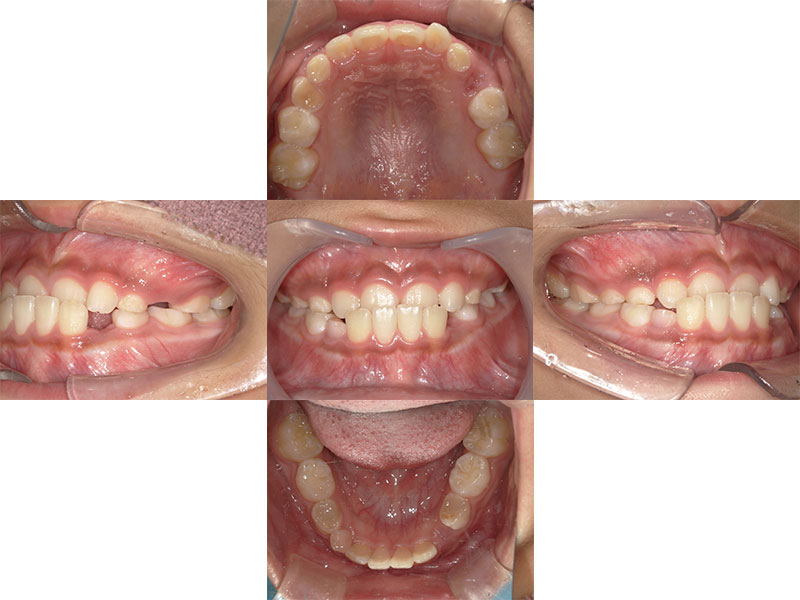

目立たない、

快適なマウスピース矯正

当院では透明で目立ちにくいマウスピース型矯正装置(インビザライン)を導入しています。iTeroという光学スキャナーでお口の中を撮影するだけで精密な歯型が採れるため、粘土のような材料での型取りは不要です。撮影したデータですぐに治療後の歯並びをシミュレーションすることも可能です。快適で負担の少ない矯正治療を始めませんか。